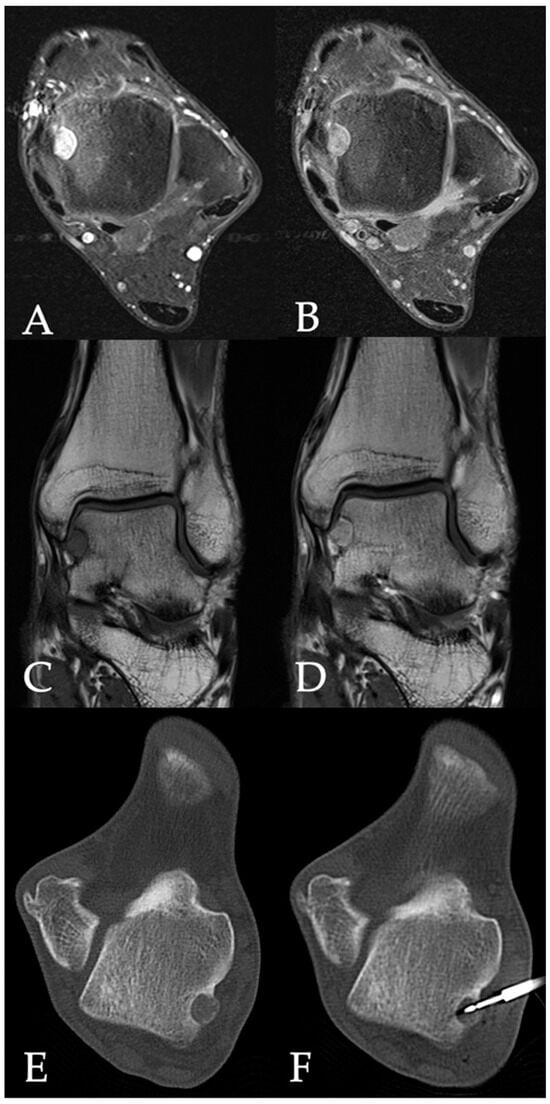

1. Introduction

2.1. Radiofrequency Ablation